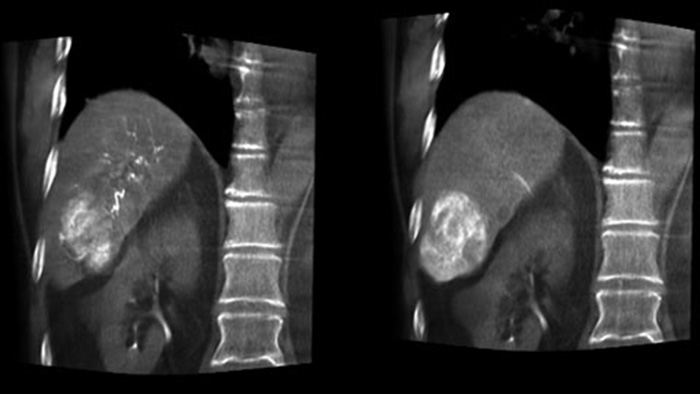

Освобождая пространство слева от пациента, CBCT Open позволяет выполнять позиционирование стола пациента со смещениемот центра и, соответственно, способствует выравниванию поля обзора3-4. Благодаря этому увеличивается охват визуализации, что помогает исследовать опухоли периферических участков печени4.

Возможность обнаружения и дифференциации узелков в печени и определения крошечных питающих сосудов играет важнейшую роль при выборе правильного лечения. Продвижение к исследуемой области с проработкой всех питающих сосудов вкупе с избирательностью обработки области поражения увеличивает шансы на успех. Возможность проверки исхода проведенной процедуры в момент нахождения пациента на столе повышает уверенность в клинических результатах.